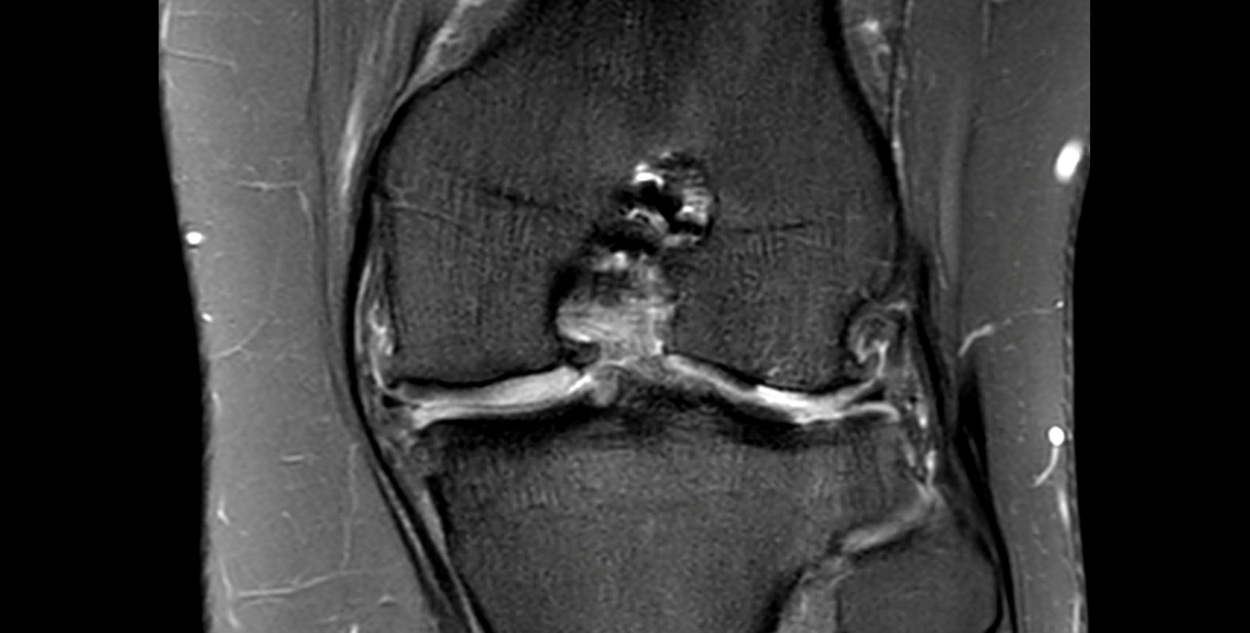

The ACL graft is ruptured with a loss of the normal ACL contour and signal. There is a focal are of full-thickness cartilage loss on the posterior, weight-bearing portion of the lateral femoral condyle. This measure approximately 15 x 10mm. There is also thinning and irregularity of the articular cartilage involving the posterior aspect of the lateral tibial plateau with a small area of full thickness cartilage loss and subchondral reactive change. These chondral changes were not present at the time of her first surgery. There appears to have been trimming of the mid and posterior thirds of both menisci. These meniscal remnants are small and irregular.